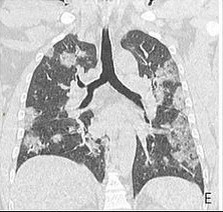

Сейчас больных COVID-19 подключают к аппарату ИВЛ в случае выраженной дыхательной недостаточности, то есть когда значительная часть легких уже поражена вирусной пневмонией. КТ-картина при этом выглядит примерно так. На фоне больших пневмонических очагов выявляются не пораженные участки легких.